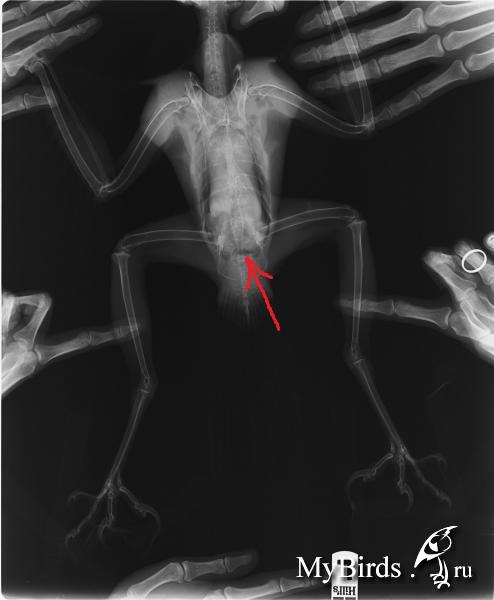

Pticelov Опубликовано 18 февраля, 2013 #100 Опубликовано 18 февраля, 2013 Может быть невнимательно прочитал тему, если так, то прошу прощения.Что у птицы с хвостом? Во время испражнения поднимает? Струя помёта нормальная (0,5 - 1 м)? Если заставить взмахнуть крыльями, хвост раскрывается в веер?У меня был подстреленный тетеревятник, который при падении повредил поясничный отдел (был сильный отёк). Пару недель птица не могла управлять хвостом и одной лапой, испражнялась не по-ястребиному ("под себя").Никого не смущает тёмное пятно а снимке?

Димулька Опубликовано 18 февраля, 2013 Автор #101 Опубликовано 18 февраля, 2013 Струя нормальная. Хвост поднимает, веером и с начала так было. А вот пятнышко и в правду смущает...

Полосатая Опубликовано 18 февраля, 2013 #102 Опубликовано 18 февраля, 2013 Нормальное пятно, как вариант - это лишь небольшое кол-во газов в кишечнике. Вы не на пятно смотрите, а на целостность позвонков - они целые, ровные, позвоночный столб не нарушен.